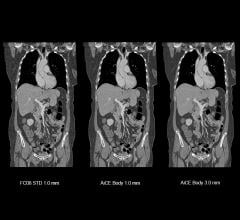

November 22, 2023 — Siemens Healthineers has announced the U.S. Food and Drug Administration (FDA) clearance of the ...